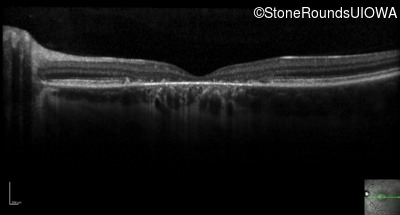

Optical Coherence Tomography - Right - 20/100 +1

Exemplar / OCT Stack